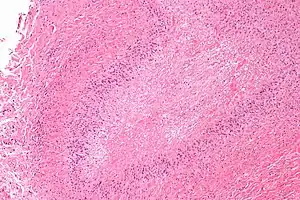

| Micrograph of a rheumatoid nodule, showing the characteristic palisading granuloma with a core consisting of necrotic collagen and fibrin. H&E stain. | |

Histological examination of nodules shows that they consist of a shell of fibrous tissue surrounding a center of fibrinoid necrosis.[13] Pea-sized nodules have one centre. Larger nodules tend to be multilocular, with many separate shells or with connections between the necrotic centers. Individual necrotic centers may contain a cleft or several centers of necrosis may all open on to a large bursal pocket containing synovial fluid.

The boundary between the necrotic center and the outer fibrous shell is made up of the characteristic feature of the nodule, which is known as a cellular palisade. The palisade is a densely packed layer of macrophages and fibroblasts which tend to be arranged radially, like the seeds of a kiwifruit or fig.[13] Further out into the fibrous shell there is a zone that contains T cells and plasma cells in association with blood vessels.[14] The histology of pulmonary nodules are similar to that of subcutaneous nodules, with central necrosis surrounded by palisading macrophages and inflammatory infiltrate.[5]